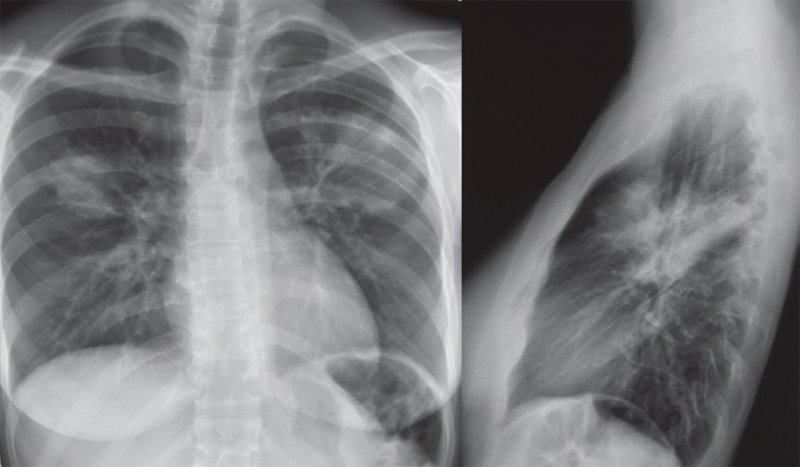

Двусторонняя полисегментарная пневмония верхних долей легких

Рисунок 4. Двусторонняя полисегментарная пневмония верхних долей легких (прямая и боковая проекции)

Усиление интерстициального компонента легочного рисунка может определяться при пневмонии с поражением интерстициальной ткани легких, что является признаком поражения перибронховаскулярной соединительной ткани и воспаления (утолщения) междольковых перегородок. При этом на рентгенограмме обнаруживаются линейные и сетчатые (ретикулярные) тени. Отметим, что при пневмонии интерстициальная и альвеолярная инфильтрация может сочетаться (см рисунок 9).

Рисунок 9. Двусторонняя полисегментарная пневмония. В верхней доле слева и в нижней доле справа отмечается малоинтенсивная интерстициальная инфильтрация по типу «матового стекла». В верхней доле справа и в прикорневой зоне отмечается более интенсивная альвеолярная инфильтрация – симптом «воздушной бронхографии» (см стрелка). В прикорневых отделах с обеих сторон и в верхней доле слева определяется усиленный интерстициальный компонент легочного рисунка с образованием ретикулярных теней